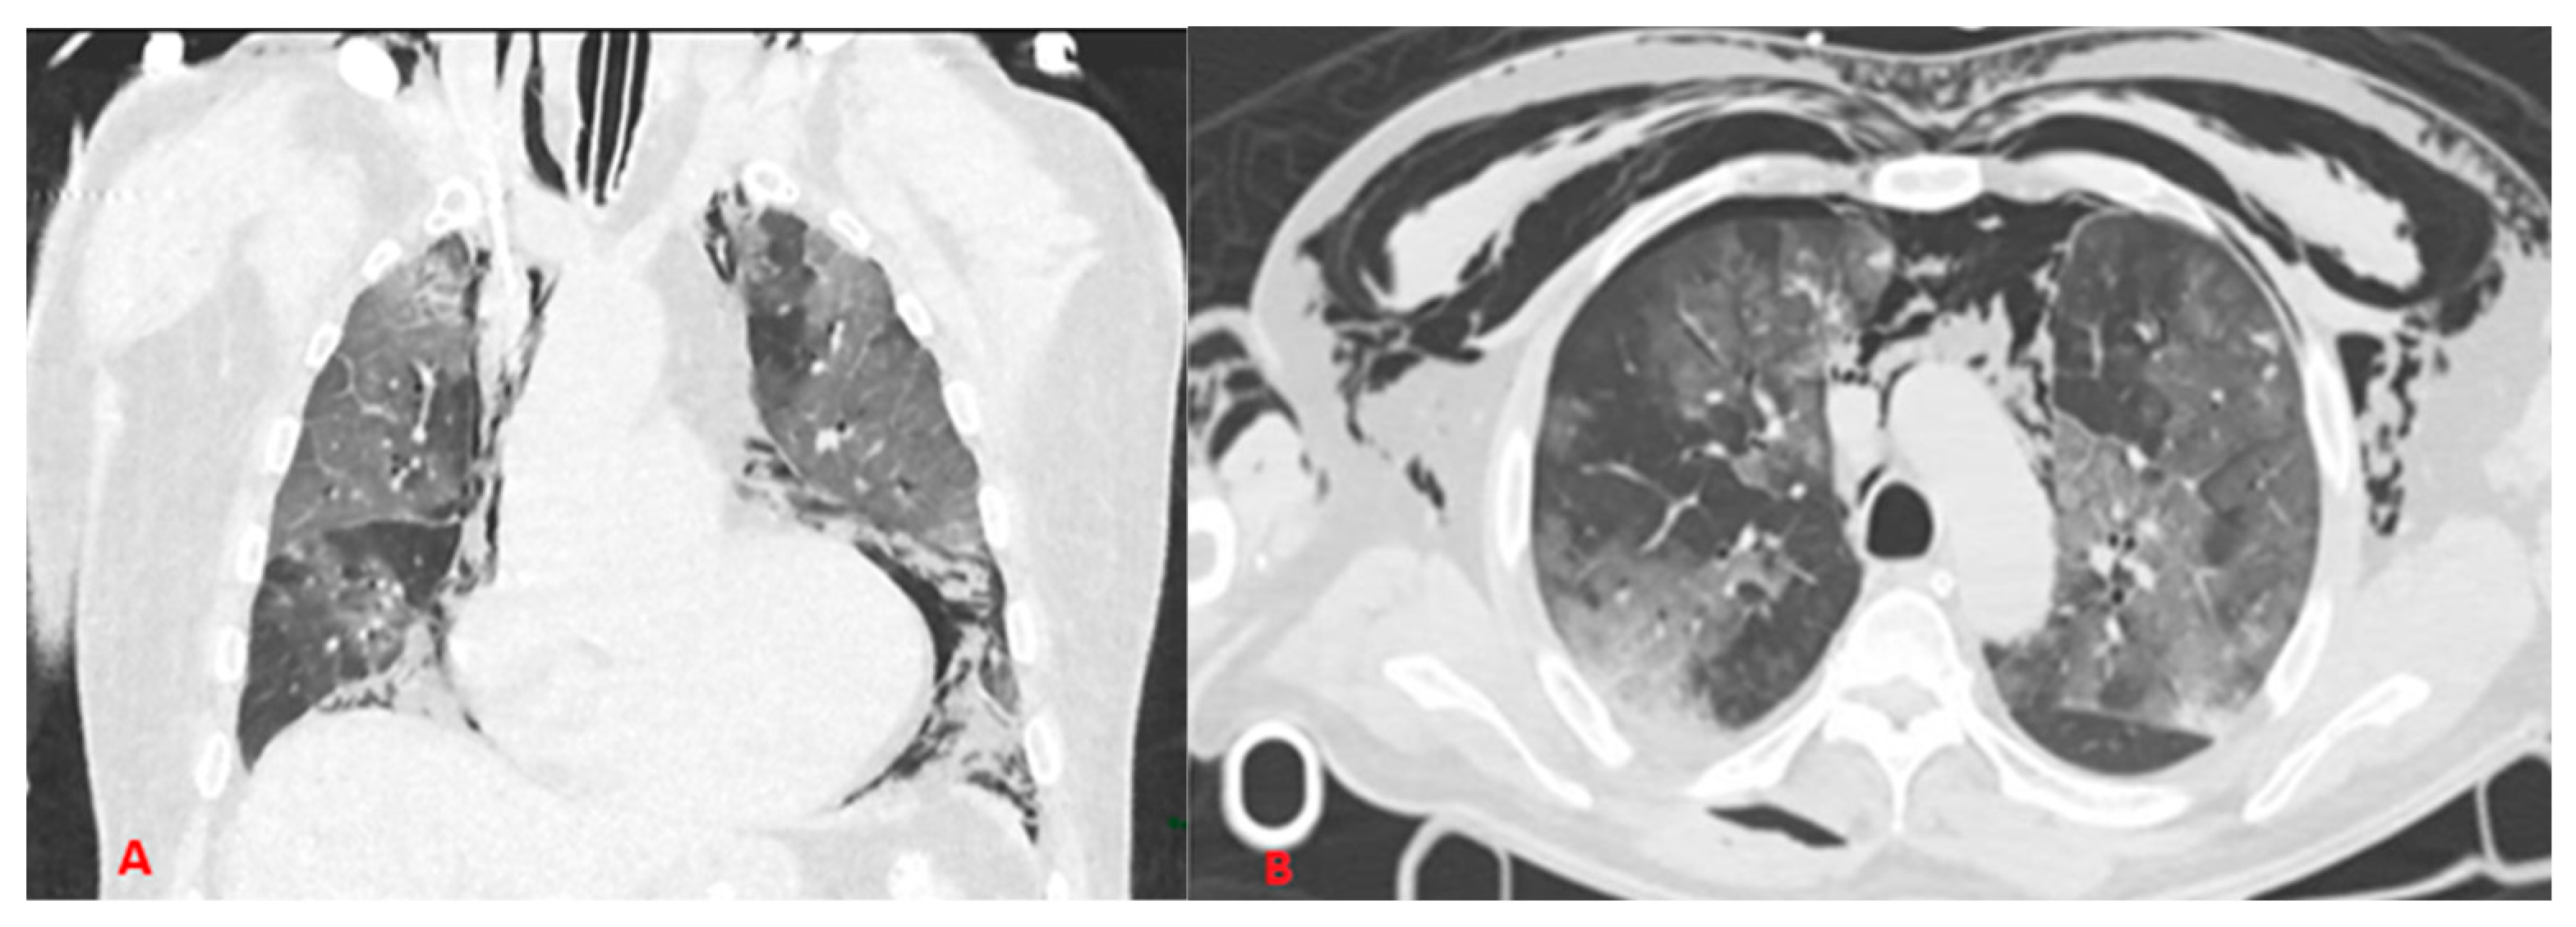

From nccommons.org

Barotrauma due to mechanical ventilation (Radiopaedia 2807928336 Axial lung window) NC Commons Barotrauma Medical Lungs It is most often due to alveolar rupture resulting in. pulmonary barotrauma can complicate mechanical ventilation. barotrauma is an important and potentially lethal complication of mechanical ventilation. the symptoms of pulmonary barotrauma include chest pain, shortness of breath, coughing, and wheezing, among others. pulmonary barotrauma is a complication of mechanical ventilation and has correlations with increased. Barotrauma Medical Lungs.

Barotrauma due to mechanical ventilation (Radiopaedia 2807928336 Axial lung window) NC Commons Barotrauma Medical Lungs the symptoms of pulmonary barotrauma include chest pain, shortness of breath, coughing, and wheezing, among others. pulmonary barotrauma is a complication of mechanical ventilation and has correlations with increased morbidity. pulmonary barotrauma can complicate mechanical ventilation. barotrauma is an important and potentially lethal complication of mechanical ventilation. It is most often due to alveolar rupture resulting. Barotrauma Medical Lungs.